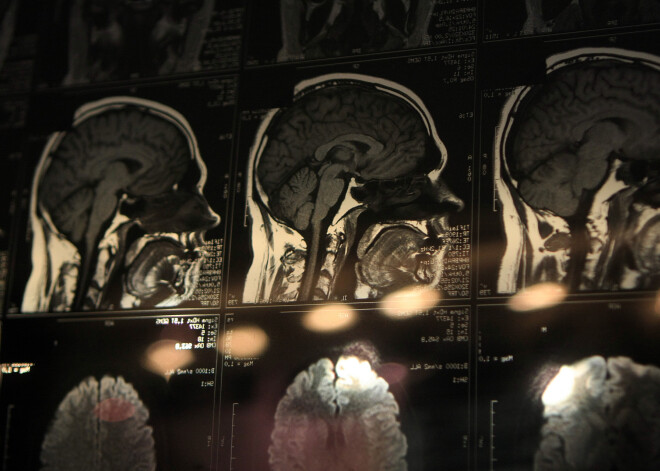

Smadzeņu pētniecības metodes var iedalīt divās lielās grupās – vai nu tiek pētīta smadzeņu struktūra, proti, tas, kā izskatās smadzenes, vai arī tiek pētīta to darbība, proti, cik augsta vai zema ir dažādu smadzeņu zonu aktivitāte.

Vislabākie rezultāti panākami, ja tiek izmantotas strukturālās un funkcionālās pētniecības metodes kopā. Pateicoties jaunākajām tehnoloģijām ir iespējams ļoti agrīni diagnosticēt dažādas problēmas, piemēram Alcheimera slimību.